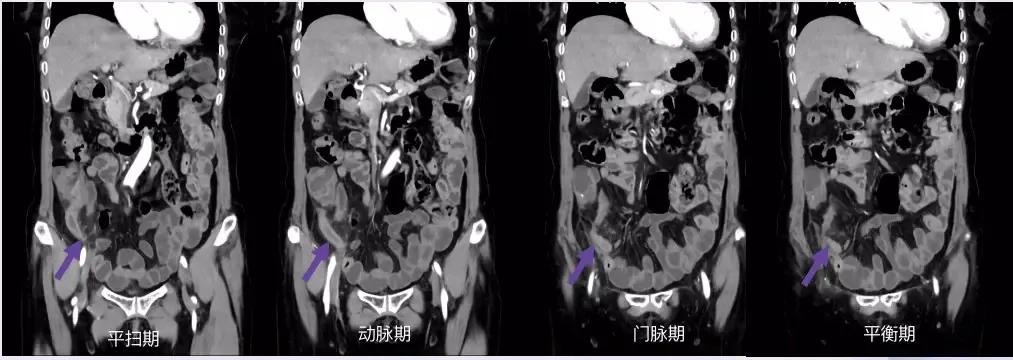

1. 回肠前位:尖端指向左上方

2. 盆位:尖端指向盆腔

3. 盲肠下位:尖端指向右下方

4. 回肠后位:在回肠后位,指向脐

5. 外侧位:位于腹腔内,盲肠外侧